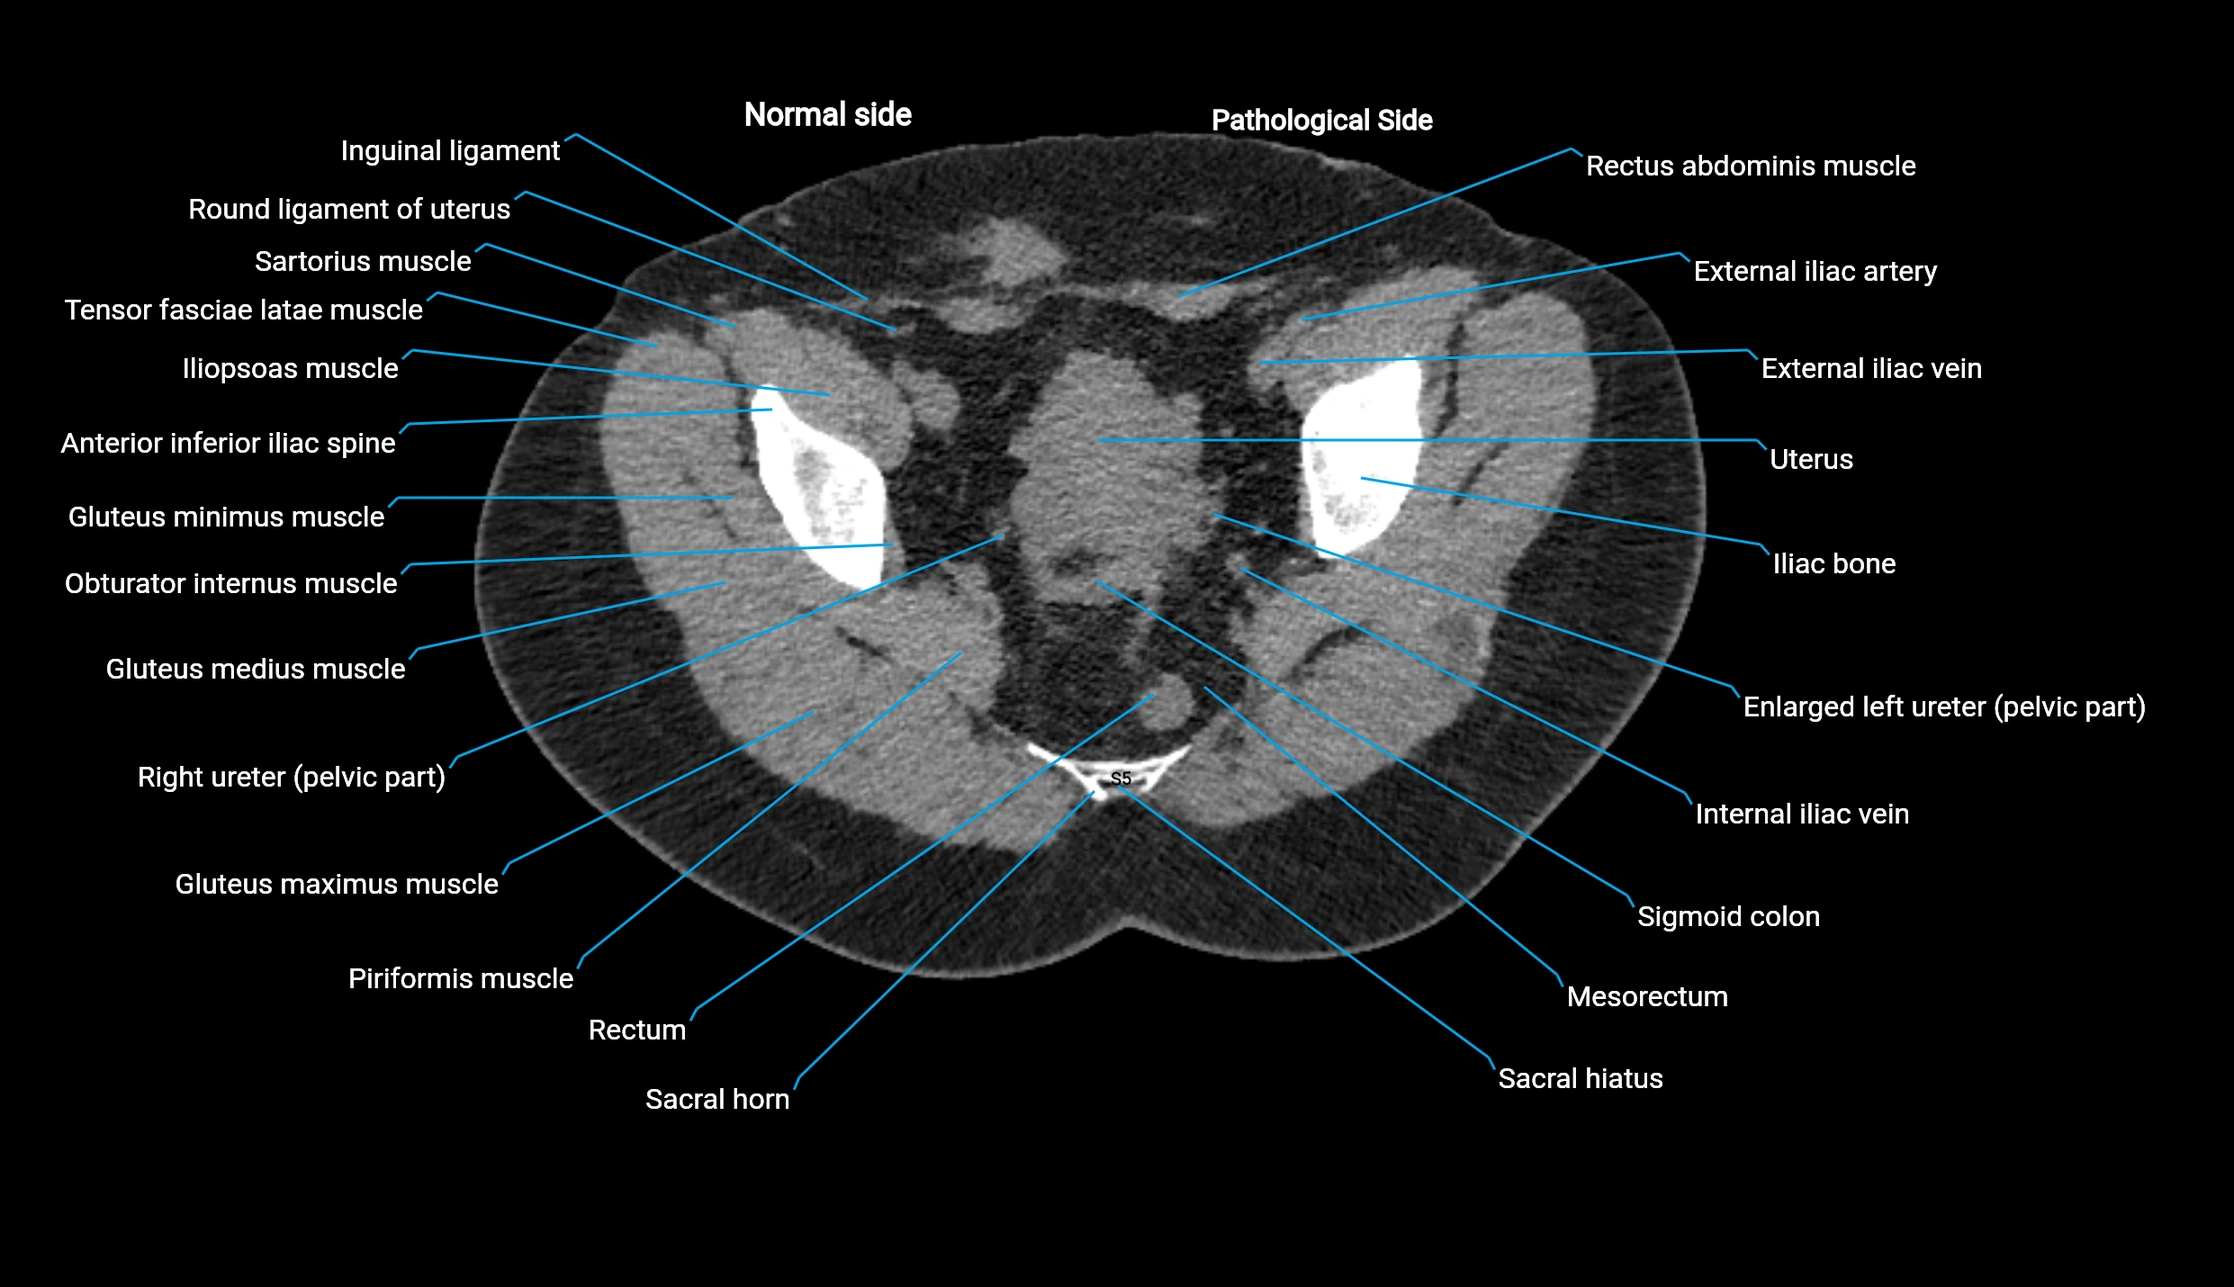

CT image

image